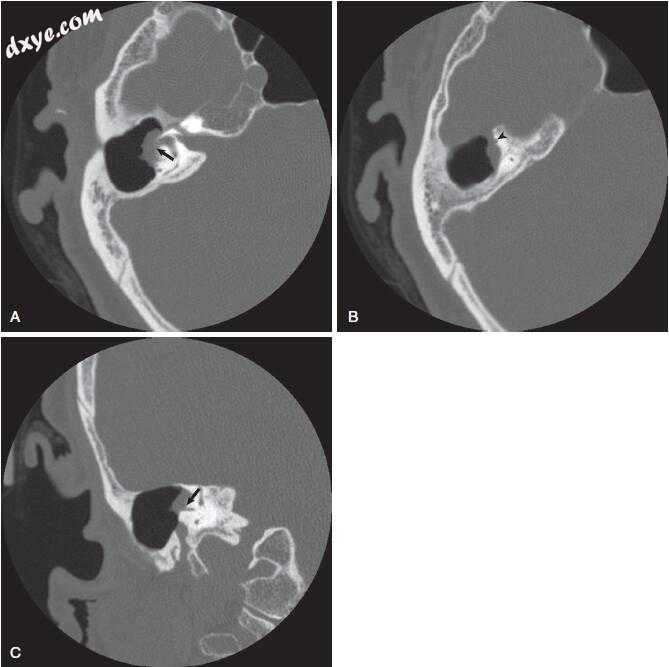

图-7. 颞骨骨扫描计算机断层扫描与Bezold脓肿患者的对比。 A,外耳道和中耳的不透明(白色箭头)。 还要注意乳突下部(黑箭头)的骨质破坏。 B,在茎突的根部(白色箭头)水平切割得更差,表明乳突尖端前部(黑箭头)的骨头破坏。 C,软组织开窗显示Bezold脓肿,在乳突尖端水平增强囊(箭头)。 D,可见脓腔(箭头)在颈部向下延伸至舌骨水平(箭头)。